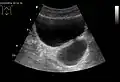

Divertículos de vejiga como se ve en la ecografía con Doppler[20]

Divertículos de vejiga vistos en ultrasonido[20]